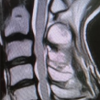

MRI of the wrist showed a large mass causing extensive osteolysis of the distal radius and extending proximally with abnormal replacement of the marrow in the distal one third of the radius. The soft tissue component of the mass involved the entire extensor tendon groups and infiltrated through the subcutaneous tissues to the dermis (Fig. 3,4,7). CT thorax abdomen and pelvis and whole body bone scan confirmed that this was an isolated lesion with no evidence of dissemination. The patient was brought to theatre for biopsy following consultation from the National Musculoskeletal Tumour Centre. Subsequent histopathological examination confirmed a B-cell non-Hodgkin lymphoma (diffuse large B-cell lymphoma -DLBCL- right wrist-stage 1EA). The patient was referred to the Haematology Service for further treatment and follow-up. She received chemotherapy (R CHOP C6 plus Rituximab and R CHOP C4) and radiotherapy (IFRT) with satisfactory results that caused the mass to shrink considerably (more than 50% after the first cycle of radiotherapy) and subsequent CT scans didn’t show any evidence of metastases. Despite her good response to the therapy, this lady died from causes not related to her primary diagnosis (pulmonary embolism).